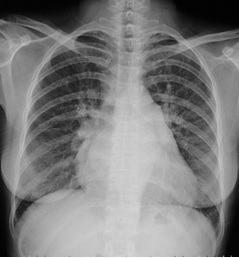

試題:根據(jù)下圖請做出正確診斷

A.正常心臟

B.心肌病(普大心)

C.風(fēng)濕性心臟病(梨型心)

D.主動脈型心(靴型心)